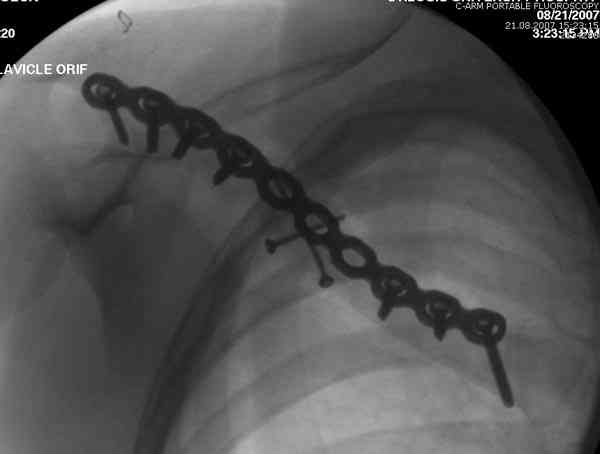

Описанный случай это больная моего партнера, мы недавно случай разбирали на нашей конференции (Morbidity and Mortality Conference аналог клинического разбора)

Выставлен как пример, к чему может привести

неудачно выбранный фиксатор.

Больные иногда пропадают из нашего поле зрения, ту больную неудачно оперировал в нашем городе специалист по спортивной медицине. Он же направил к нам после удаления фиксатора.